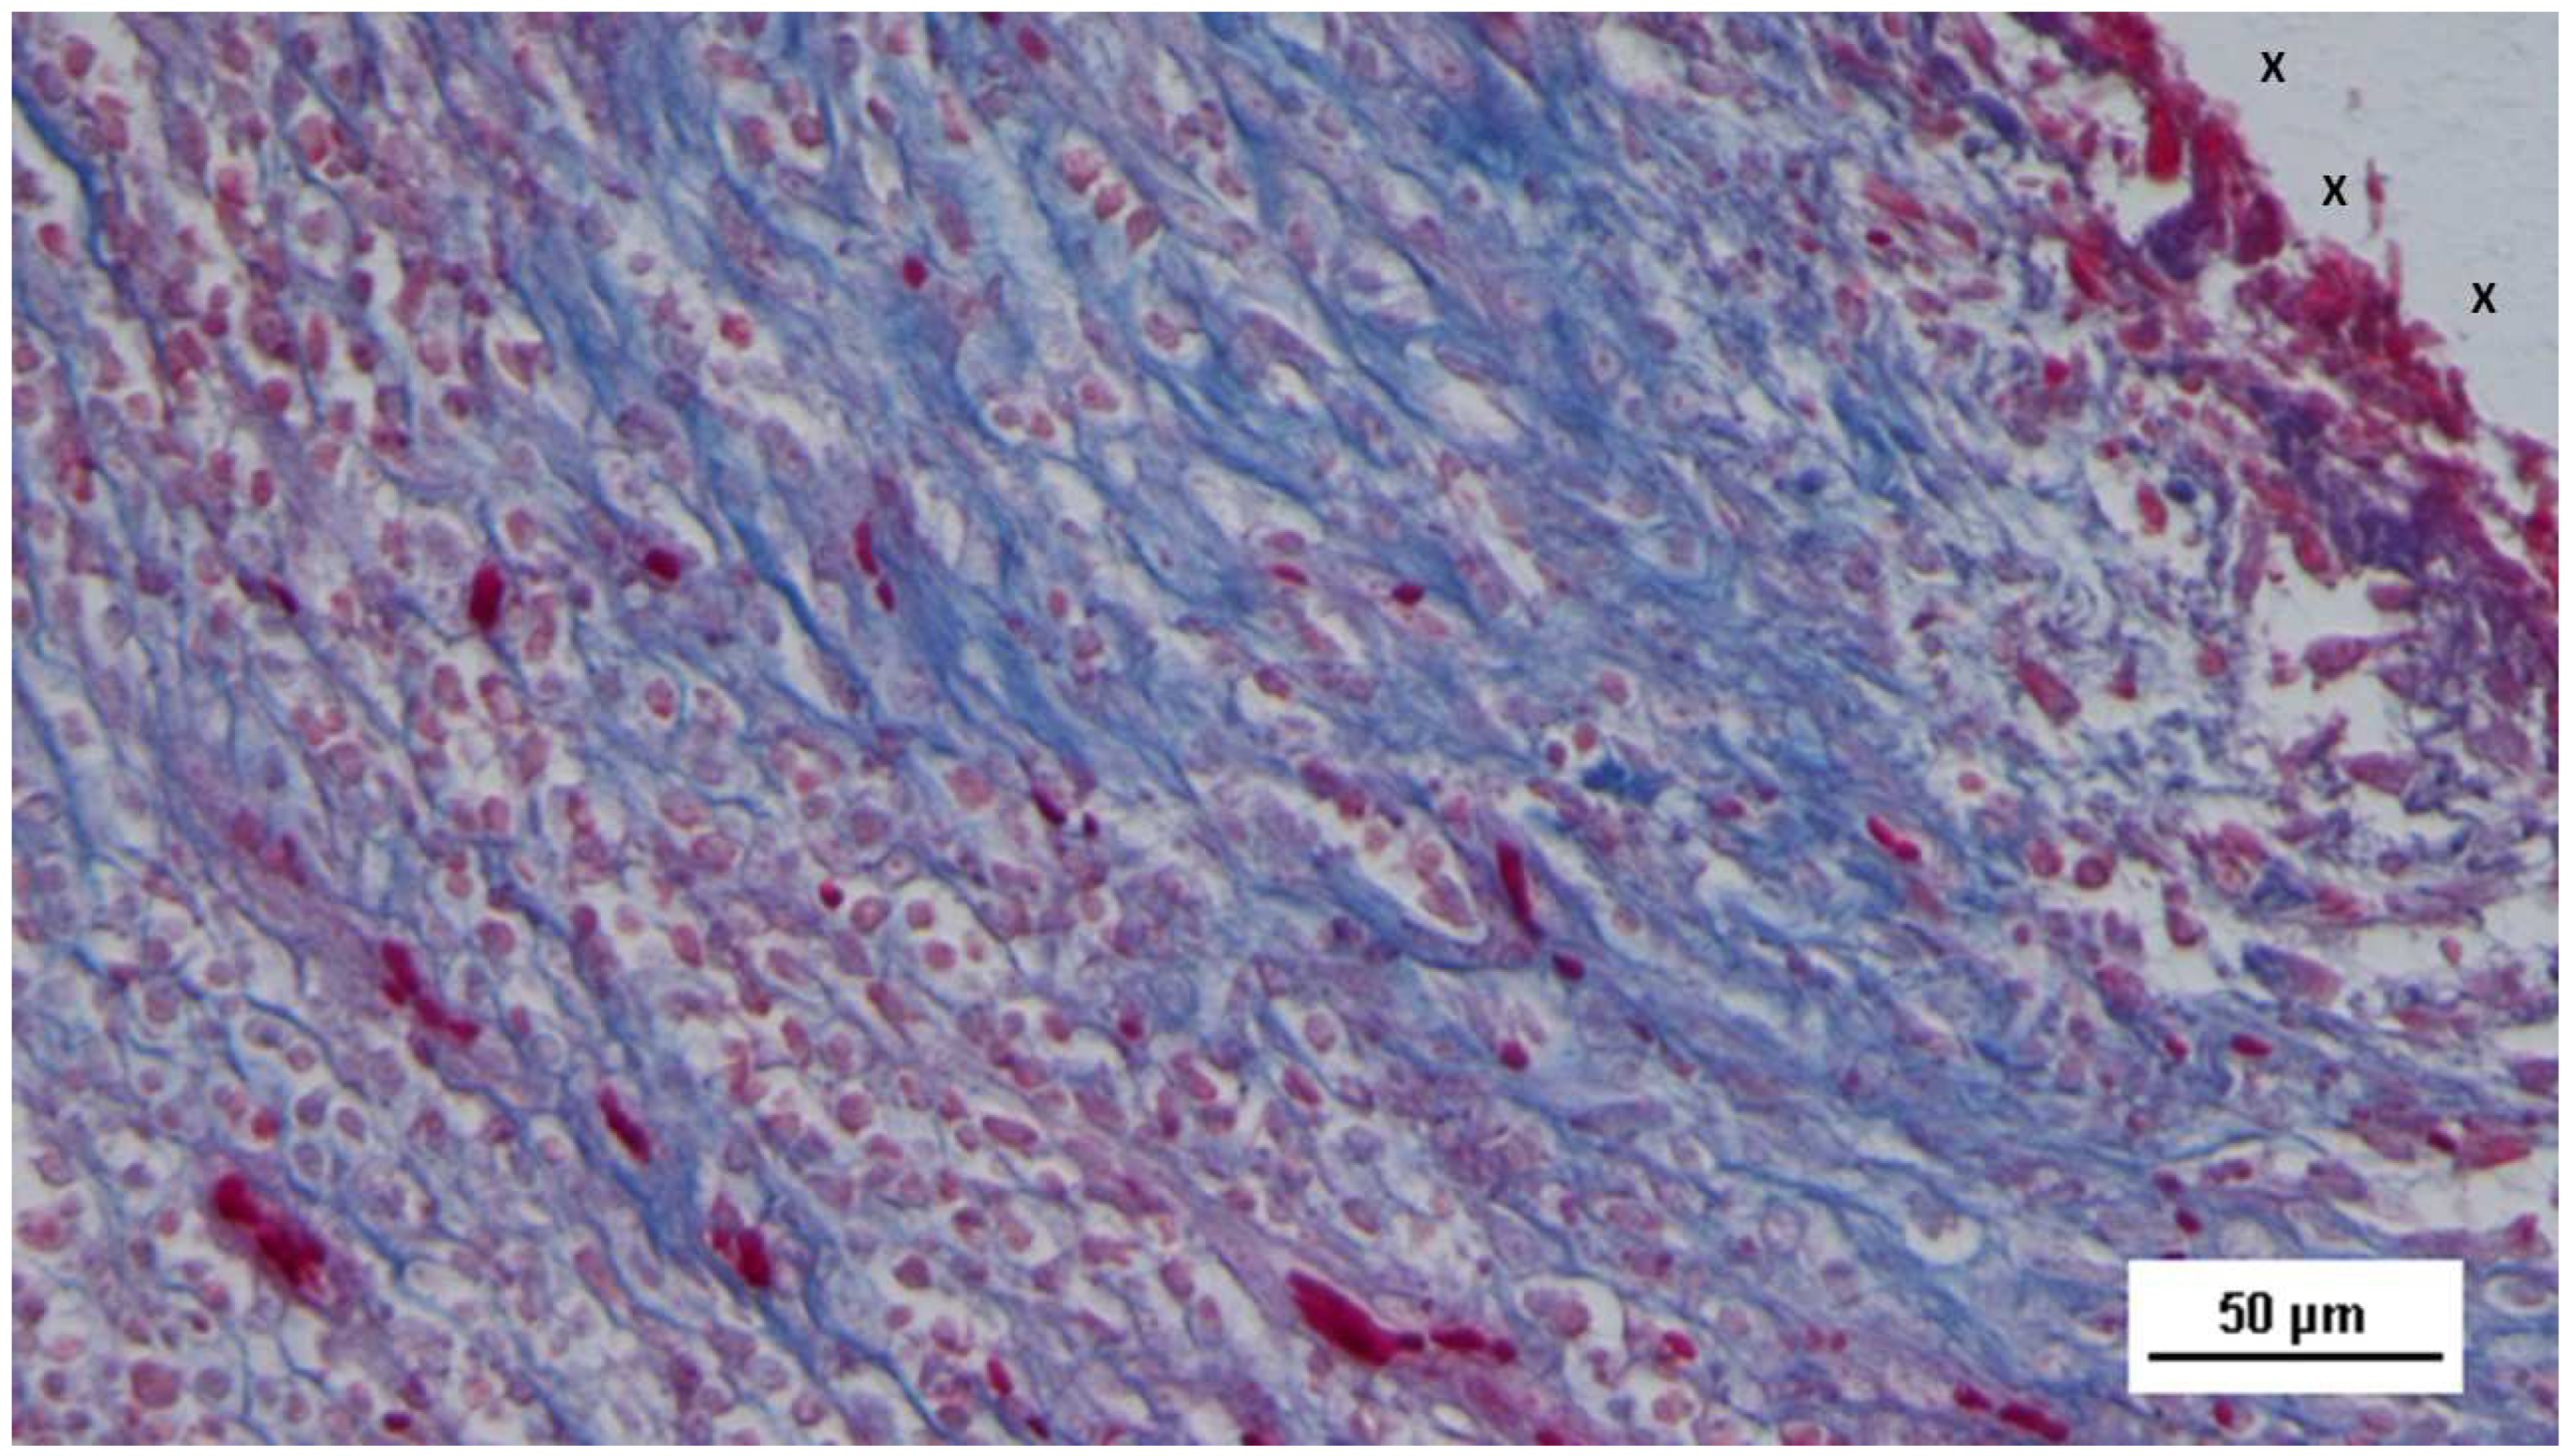

Table 16 The nascent myocytes exhibited prominent nucleoli, vesicular nuclei, and moderate basophilia, indicative of early myocytic differentiation. By the midterm phase, the number of NGF-positive cells had increased in the TPE fabric of the scaffold (Figure 17), corresponding with a more extensive and organized development of muscle fibers and larger bundles of muscle cells interspersed throughout the connective tissue adjacent to the scaffold. The muscle fibers showed small, spindle-shaped nuclei and eosinophilic cytoplasm, characteristic of progressing myocyte differentiation (Figure 18).

Figure 16. Biopsy specimen excised 5 weeks post-implantation (Short term - ST). Viable connective tissue (stained in blue) surrounds developing muscle bundles (stained in red) in early stages near the TPE fabric of the 3D scaffold (X). AM 200X.

Figure 18. Tissue specimen removed 3 months post-implantation (Midterm - MT). Multiple developing muscle bundles (red staining) surrounded by viable connective tissue (colored in blue) are seen close to the 3D scaffold (X). AM 100X.